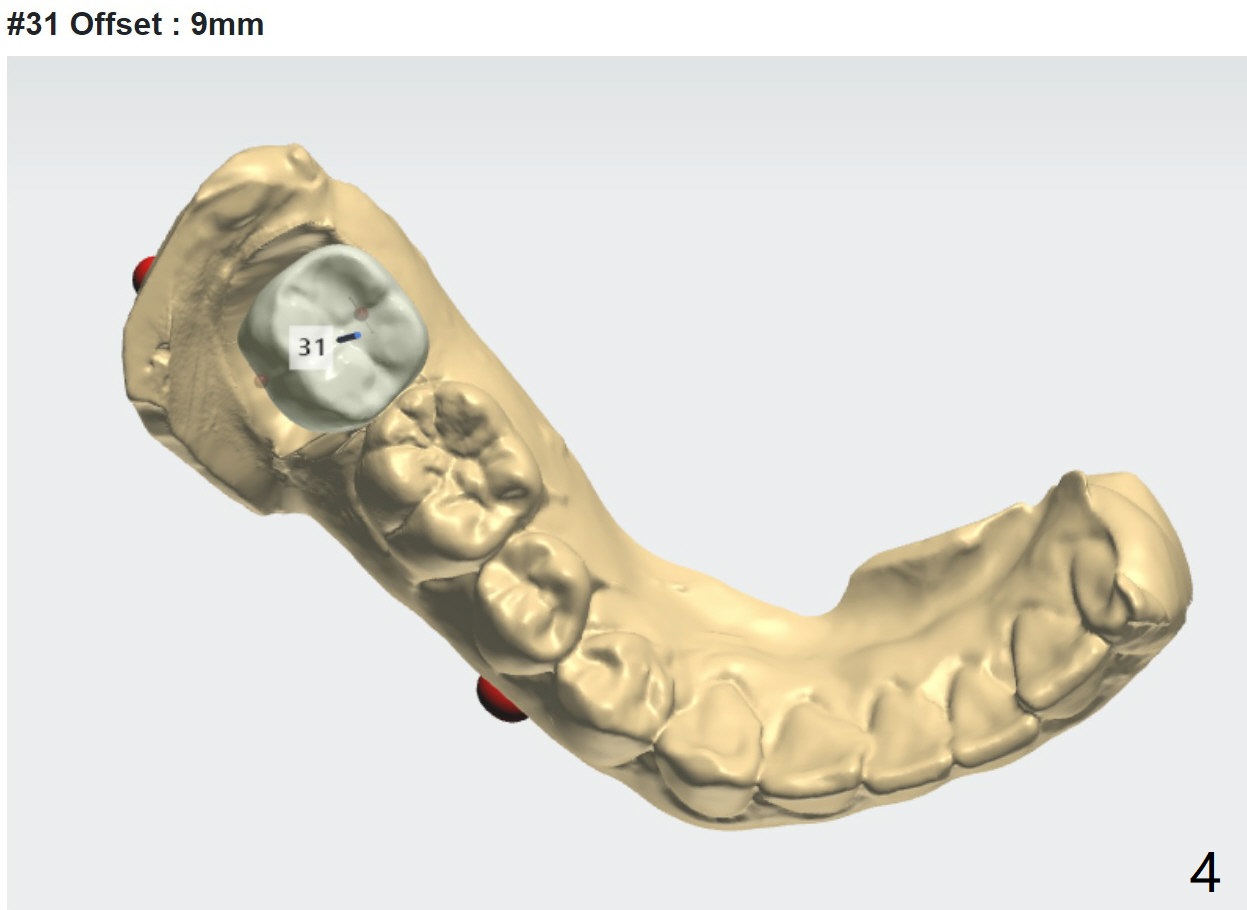

11.5 mm Implant for Lower 2nd Molar

A 30-year-old man wants #31 extracted for implant after the same treatment finished for #18.